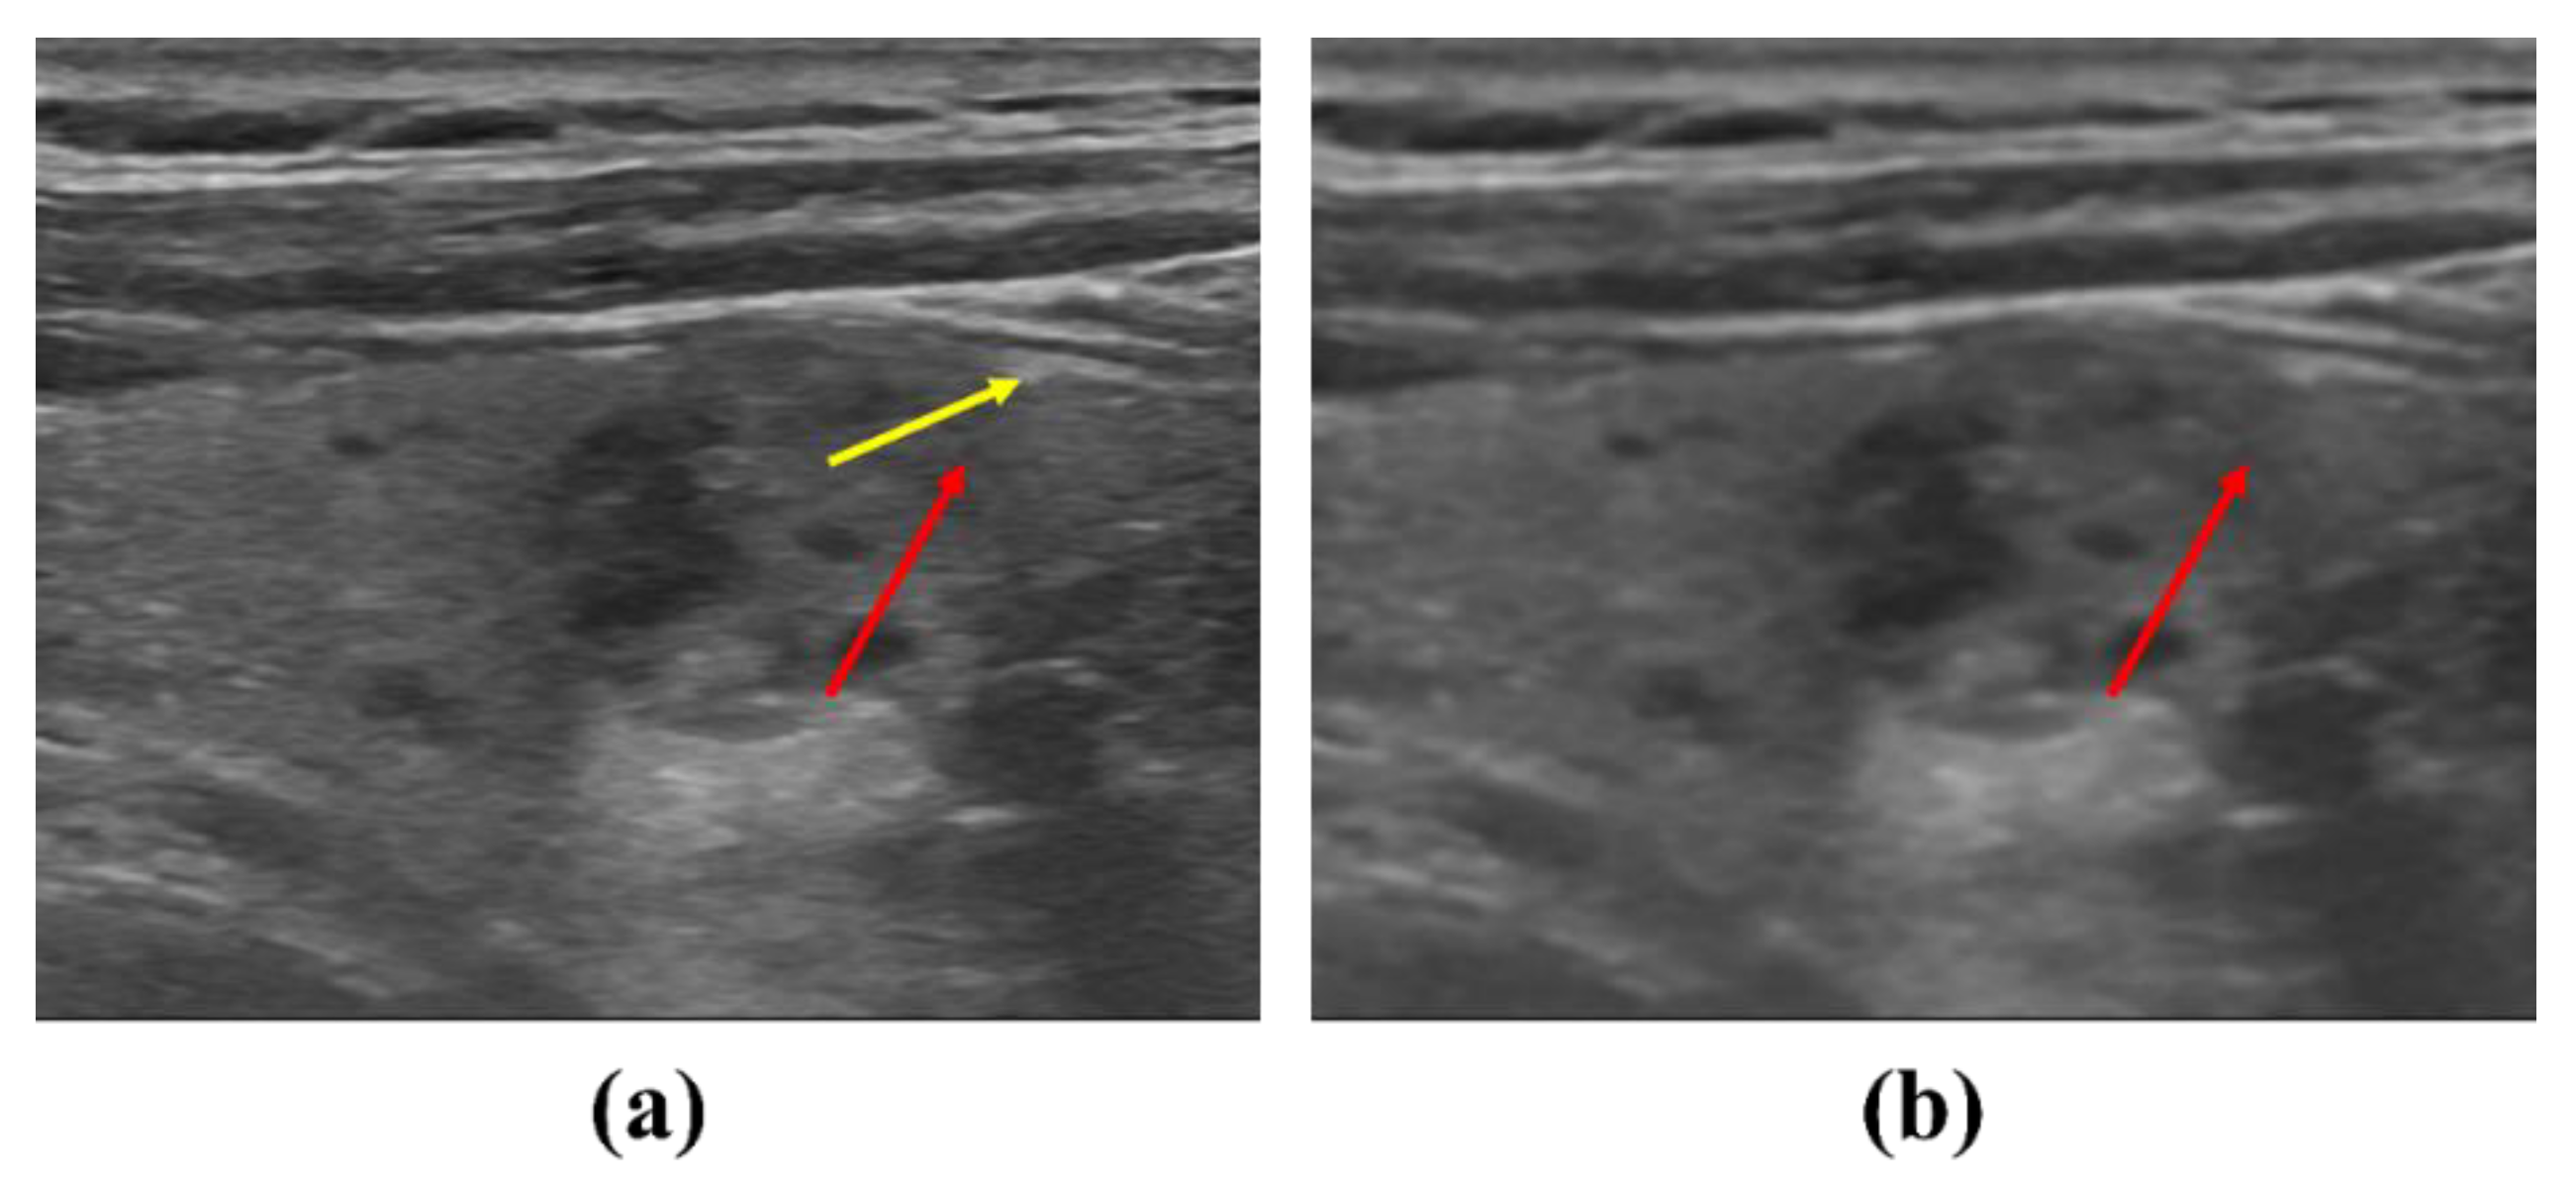

The use of proposed NLM noise-reduction algorithm in diagnostic ultrasound imaging is expected to help diagnose thyroid diseases and increase the diagnostic efficiency. Figure 8 shows the results for the proposed NLM noise-reduction algorithm applied to an ultrasound image of a thyroid nodule patient after each smoothing step. The lesion was visually observed in all stages of low, middle, and high smoothing using the NLM noise-reduction algorithm. In addition, the proposed algorithm may be useful when the diagnosis is difficult since the margin is unclear when following up on the changes in the thyroid mass size. The margin part was observed more clearly when the high smoothing step was applied to the thyroid ultrasound image than with the low smoothing step, and we expected that the size measurement accuracy of the mass part would be improved. Figure 9 is an ultrasound image of the thyroid nodule in order to observe in more detail the margin change with and without algorithm application (red arrow: margin of actual nodule, yellow arrow: part that can be mistaken for margin). As shown in Figure 9a, it can be seen that the margin of the thyroid nodule is not clear in the original ultrasound image before the denoising process. However, in Figure 9b, when the NLM noise-reduction algorithm based on high smoothing is used, we can confirm that the margin is relatively clearly revealed.

Figure 9. Ultrasound images to observe changes in the margin of the thyroid nodule: (a) noisy image and (b) NLM denoising with high smoothing. The red arrow means the actual exact nodule margin, and the yellow arrow means the margin that can be misunderstood.